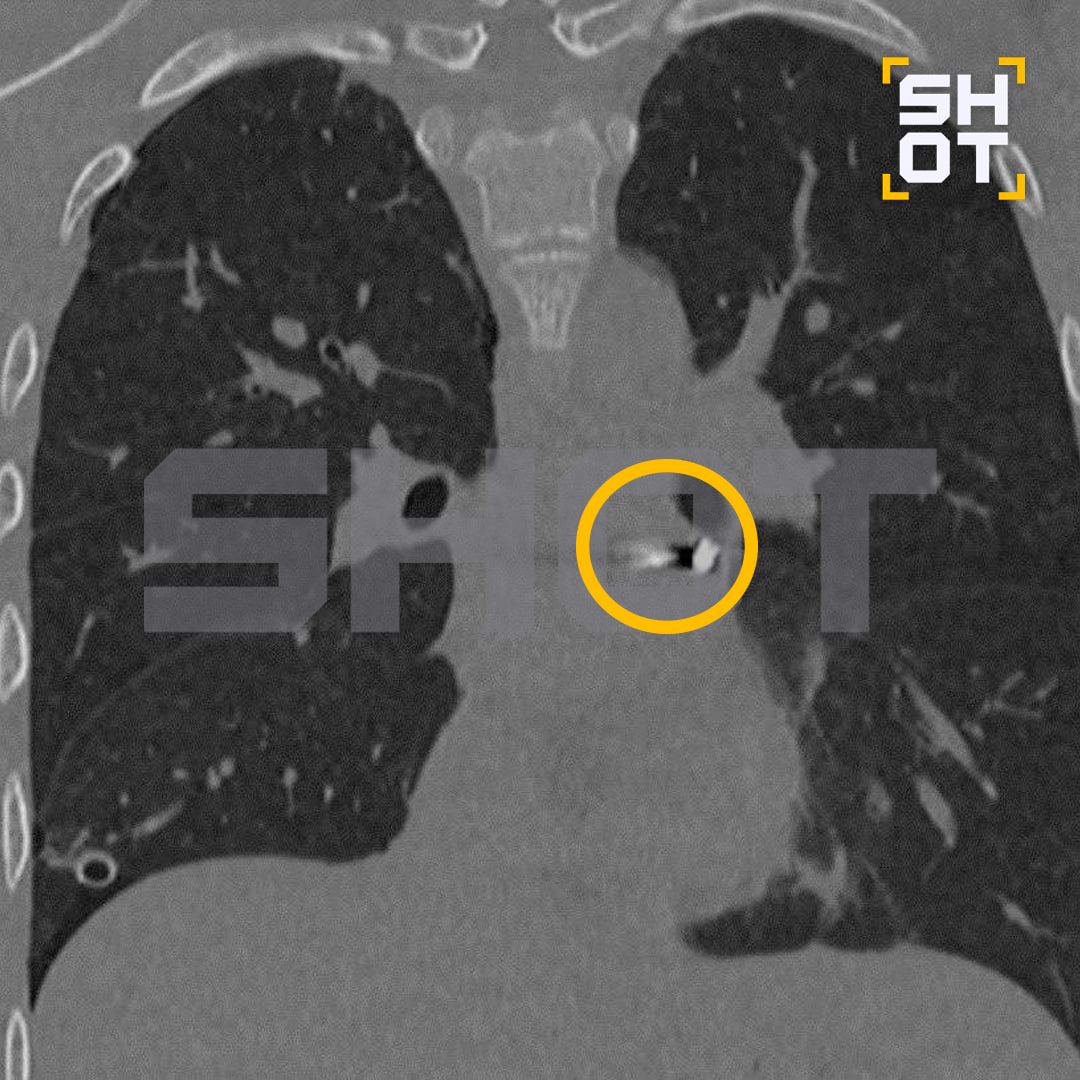

16-летнего подростка с проникающим ранением груди экстренно привезли в Детский центр им. Рошаля. Он пошёл пострелять вместе с пацанами и схватил пулю сам. Медики обнаружили её в полости перикарда — наружной оболочки сердца. Пострадавшего отправили на срочную операцию.

Хирурги работали буквально в миллиметрах от жизненно важных структур. Особенно сложно, по словам врачей, было манипулировать инструментами в условиях постоянного движения сердца. В итоге пулю удалось извлечь без единого разреза — вмешательство было малоинвазивным.